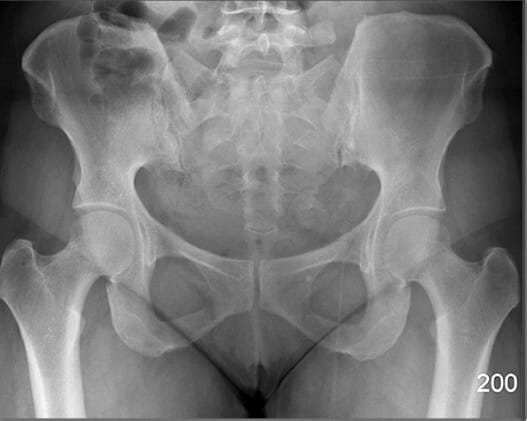

Pelvic Region

PELVIS